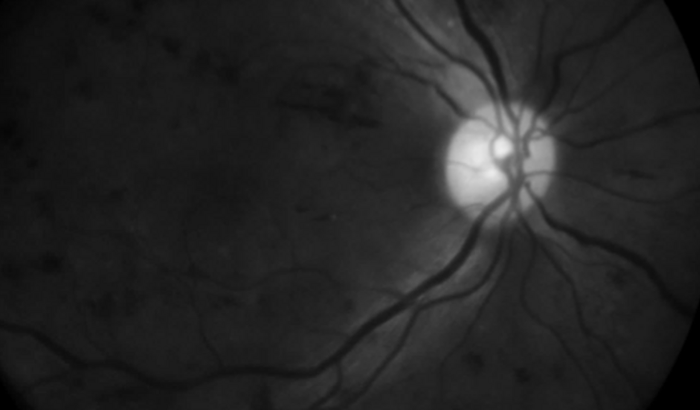

Caros colegas venho atrás desta vaquinha pedir ajuda para nossa colega Andreia da maternidade HUMAP, que está com lesões na retina (deslocamento da retina e muita hemorragia). O tratamento é uma medicação que faz somente em centro cirurgico chamado Avastin e os lasers pra conter o sangramento. Só a medicação 2.500$ cada olho e os lasers 3 sessões de 600 cada sessão. Desde já muito obrigado.